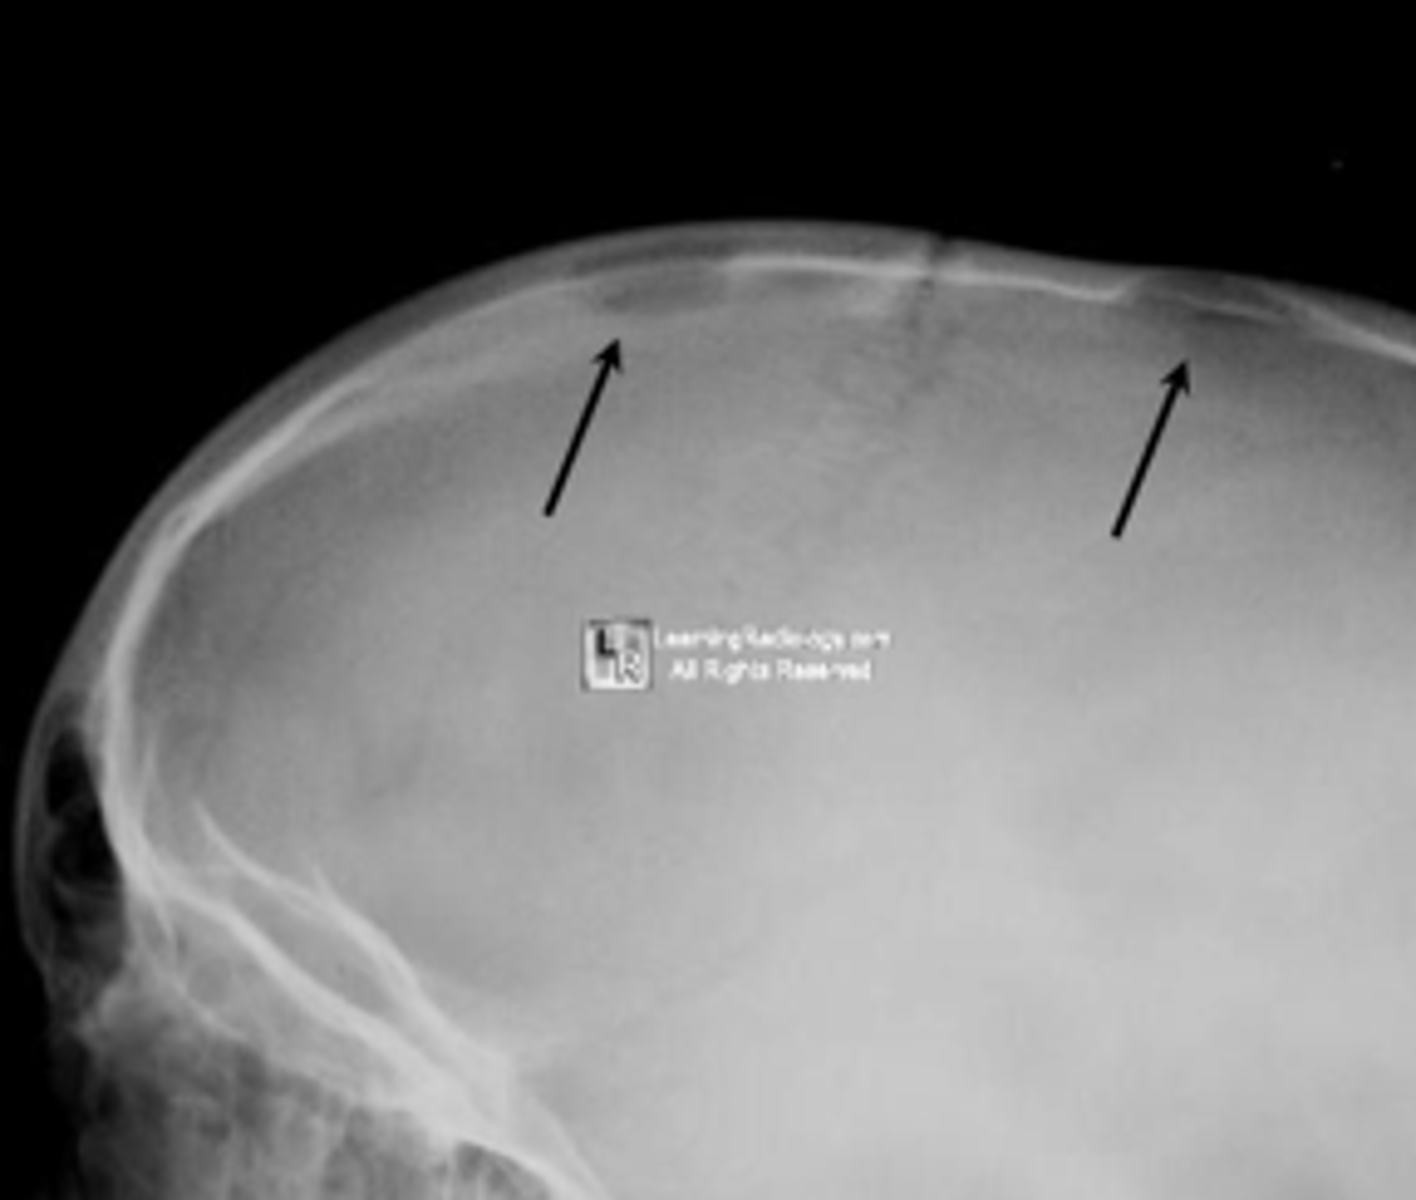

Beveled edge

ID radiographic feature of eosinophilic granuloma in the skull

<p>ID radiographic feature of eosinophilic granuloma in the skull</p>